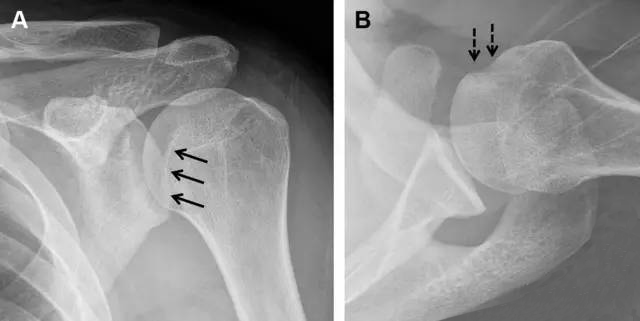

图6 肩关节前脱位伴有 Hill–Sachs 和 Bankart 损伤:(A~C)肱骨头后外侧撞击骨折,白色箭头所示为骨折的内侧边界;(A)内旋位前后位片,(B)「V」形压缩骨折的下边界(虚线短箭头),(C)Garth 位(轴向投影)示 Hill–Sachs 损伤(虚线和实线折箭头),特别是对骨性 Bankart 损伤的诊断有帮助。(D、E)MRI 进一步证实了损伤

图7 肩关节后脱位伴有反 Hill–Sachs 损伤。(A)外旋位前后位片可见一硬化带(黑箭头),此「凹槽征」与肱骨头关节面平行;(B)腋位片进一步证实了骨折的存在